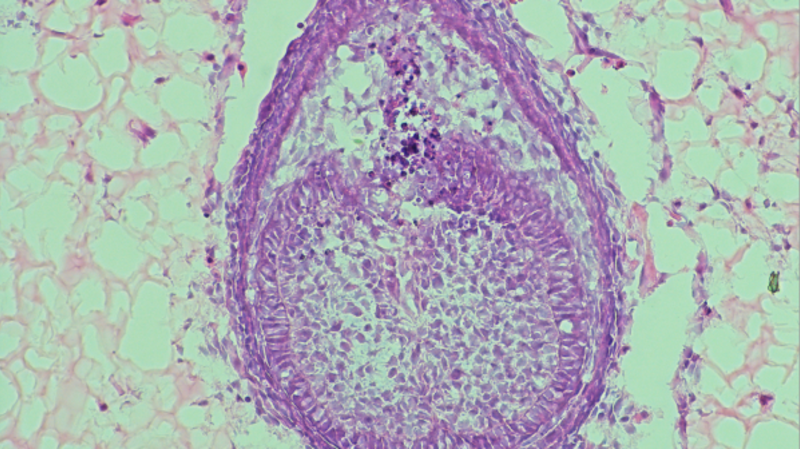

Researchers are working quickly to develop human teeth in the laboratory.

Advancements in Lab-Grown Teeth Technology It’s no secret that dental visits can be nerve-wracking for many. Replacing a tooth usually involves surgery, where a titanium screw is placed into the jawbone, followed by a long wait as it fuses into an artificial root before a crown is secured on top. Not exactly a pleasant experience, […]